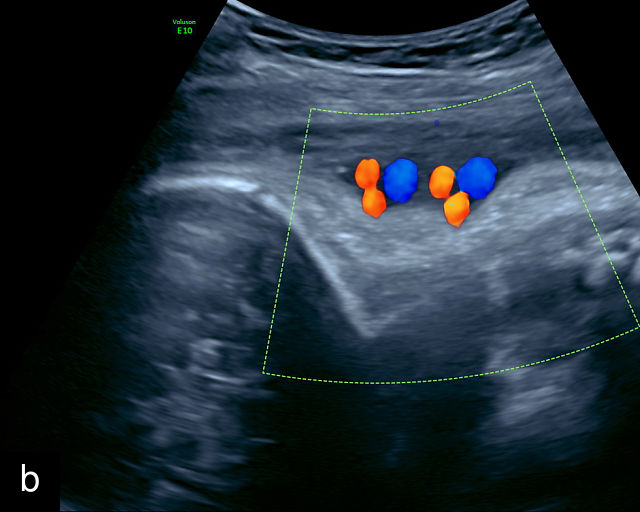

Accessory placental lobes

While most placentas consist of a single disc with several cotyledons, some placentas may have two or more separate lobes. These variations can include a bilobate placenta, where two lobes of roughly equal size are present, or a main placental body accompanied by one or more smaller accessory or succenturiate lobes (Figure 4).21,22,23,24 The cord insertions in these pregnancies are often velamentous or marginal, and blood vessels always traverse the membranes between the placental lobes. When these connecting vessels pass over the cervix, the condition is classified as Type- 2 or Type- 3 vasa previa.25,26,27,28,29,30

Accessory placental lobes. (a) Color Doppler transabdominal ultrasound image depicting a bilobed placenta with an anterior (a) and posterior (p) lobe, into which the cord inserts. (b) Grayscale ultrasound with color flow Doppler showing a bilobed placenta with anterior (a) and posterior (p) lobes. Color flow Doppler shows unprotected fetal vessels traversing the membranes between the lobes (arrow). (c) Grayscale ultrasound showing a bilobed placenta with anterior (a) and posterior (p) lobes.

The sonographic features of a bilobed or succenturiate-lobed placenta include the presence of two distinct placental masses, typically one anterior and the other posterior, which may vary in size or be of equal size.21,22,23,24,26,31,32,33 These masses are connected by blood vessels, which can be visualized using color flow Doppler (Figure 4).28

It is crucial to confirm that the masses are truly separate and not connected as part of a single lateral placenta, which may be mistaken for a bilobate placenta. Additionally, careful scanning should verify that both masses share similar echogenicity to distinguish true placental tissue from other structures such as subchorionic hematomas, myometrial contractions or uterine fibroids, which can mimic accessory lobes. Prominent placental lakes may also be observed between the lobes.23,26

The placental cord insertion in these cases is often velamentous and may be located between the placental lobes (Figure 4b; Video 2). In rare cases, furcate insertion, in which the cord vessels branch before reaching the placental tissue, between the lobes has been reported.24

In most cases, pregnancies with accessory lobes have favorable outcomes in the absence of vasa previa. However, because accessory lobes are strongly associated with vasa previa, transvaginal ultrasound with color Doppler imaging is recommended whenever they are identified.3,4,25,28,34,35,36